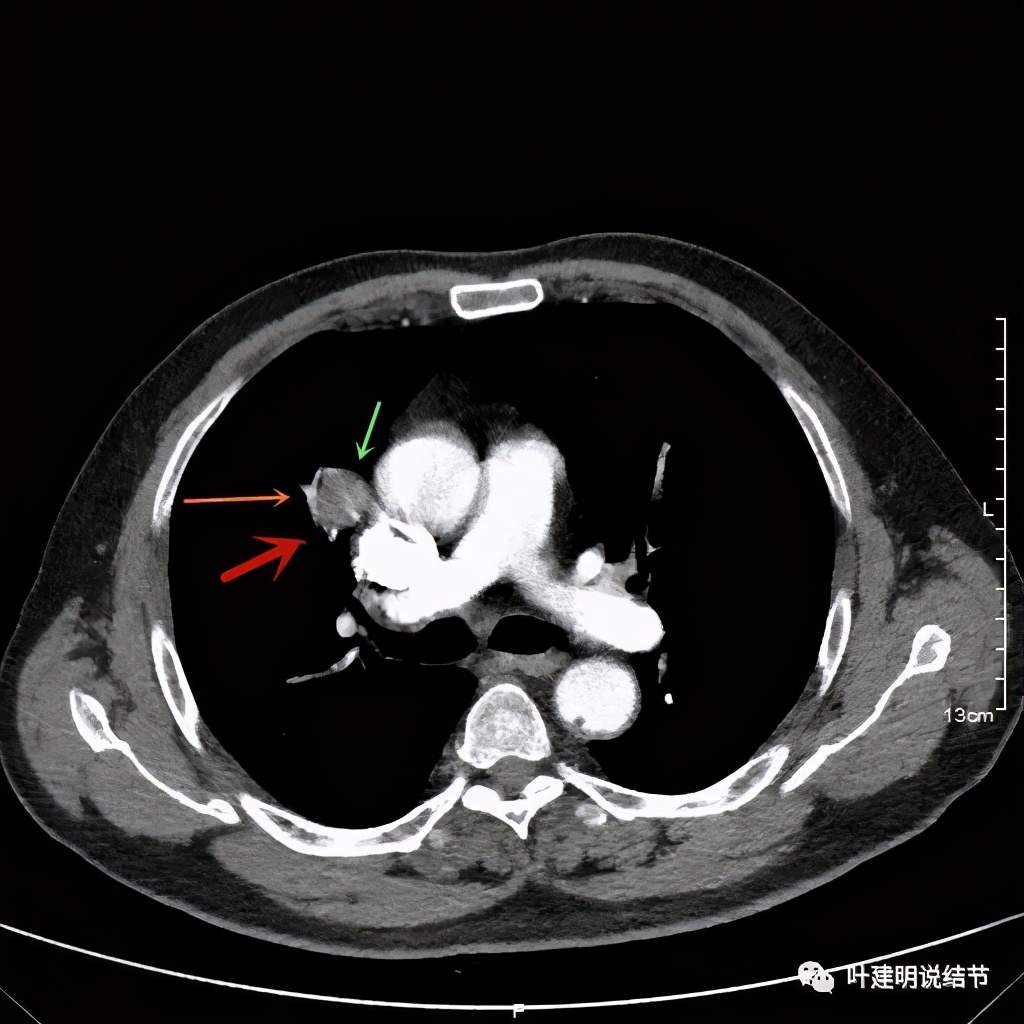

上图示病灶边缘过于光滑(绿色);局部有点状钙化(蓝色)

上图示病灶边缘过于光滑(绿色);血管贴边(桔色);

上图示病灶边缘过于光滑(绿色);血管贴边走行(桔色)

以上几图也示病灶边缘过光(绿色);血管贴边,感觉没受侵犯(桔色)

事前来看,达2.4厘米的不均质实性肿块,增强有轻度不均匀强化,血管贴边走行,支气管疑有截断,恶性不能除外,而且可能性较大。但现在经过手术已已经证实是错构瘤的情况下,我们回头来看,其实有许多不符合恶性的地方: